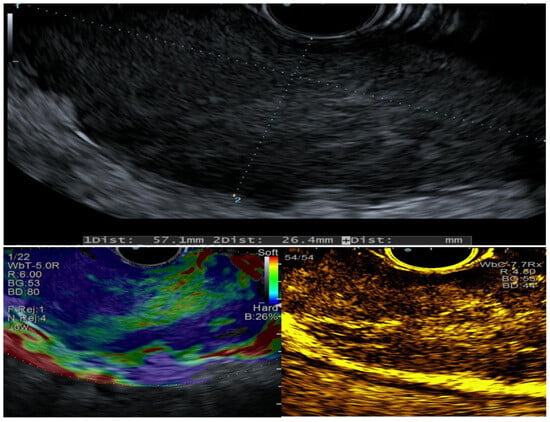

3. Clinical Case